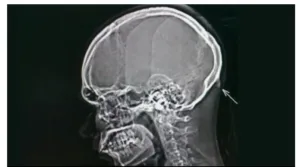

¿Es cierto que el uso de las tecnologías está cambiando algunas partes del cuerpo del ser humano? En este episodio te hablaremos del estudio que se está realizando con miles de radiografías. El cambio tecnológico sigue sorprendiéndonos.